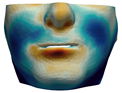

3.3. Simulation Error and Performance

4.1. Analysis of Simulation Accuracy

- Chin. Overall, the amount of error at the chin area is very low. This could be explained by the fact that the skin at the chin is very thin, and the coupling to the mandible makes the simulation highly predictive.

- Lips. In other regions, such as the lips, skin slides strongly over the underlying bones and teeth, and the deformation result is more difficult to predict. Overall, we observe higher variability in the error at the lips, and also some patients with higher error.

- Nose. The quality of the prediction of the deformation of the nose varies strongly across patients. In this case, the variability may depend on the type of surgery performed on each patient’s anterior nasal spine. This type of surgery is not easy to identify in the post-operative CBCT image due to the presence of bone grafts or fixation plates.

- Neck. Finally, we observe large error in the neck area (e.g., patients M5 and M8), and specifically at the junction point between the submental area and the neck (“C point” or “cervical point” in cephalometric analysis). This error was accounted for in our quantitative analysis, which negatively biased the overall results. However, this area is not of special interest to orthognathic surgeons. The deformation is known to be produced by a retraction of skin after surgery, but surgeons do not account for this effect during pre-operative planning.

- Segmentation of the maxilla and mandible. For all patients, the highest error (except for the neck, which is not clinically relevant as discussed above) appears near the cut areas, both of the maxilla (e.g., patients M5 and M7) and the mandible (e.g., patients M1 and M3). This is probably due to the presence of fixation plates and/or bone grafts in the real result (e.g., patient M10, whose maxilla was not segmented, but where the presence of bone graft has been confirmed by the surgeon who carried out the intervention). As a consequence, patients with a segmented maxilla and/or mandible show in general larger error than those without segmented bones. However, the smooth coupling method proposed in Section 2.3.3 reduces considerably the error in cut areas, as shown in Figure 2.